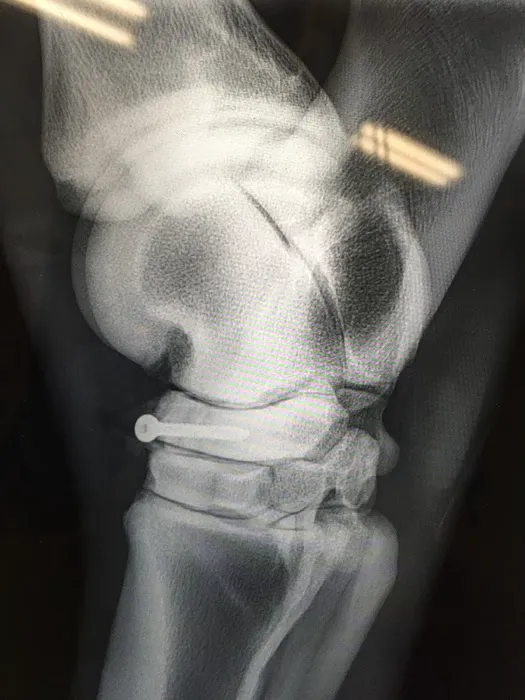

- Diagnostic Imaging: Utilizing state-of-the-art technology, including Imaging Digital Radiography, for accurate diagnosis of injuries and medical conditions.

- Advanced Diagnostics for Lameness: Specializing in Lameness & Sports Medicine, the practice uses advanced Diagnostic Imaging, including Digital Radiography, to pinpoint performance-limiting issues.

- Imaging Digital Radiography